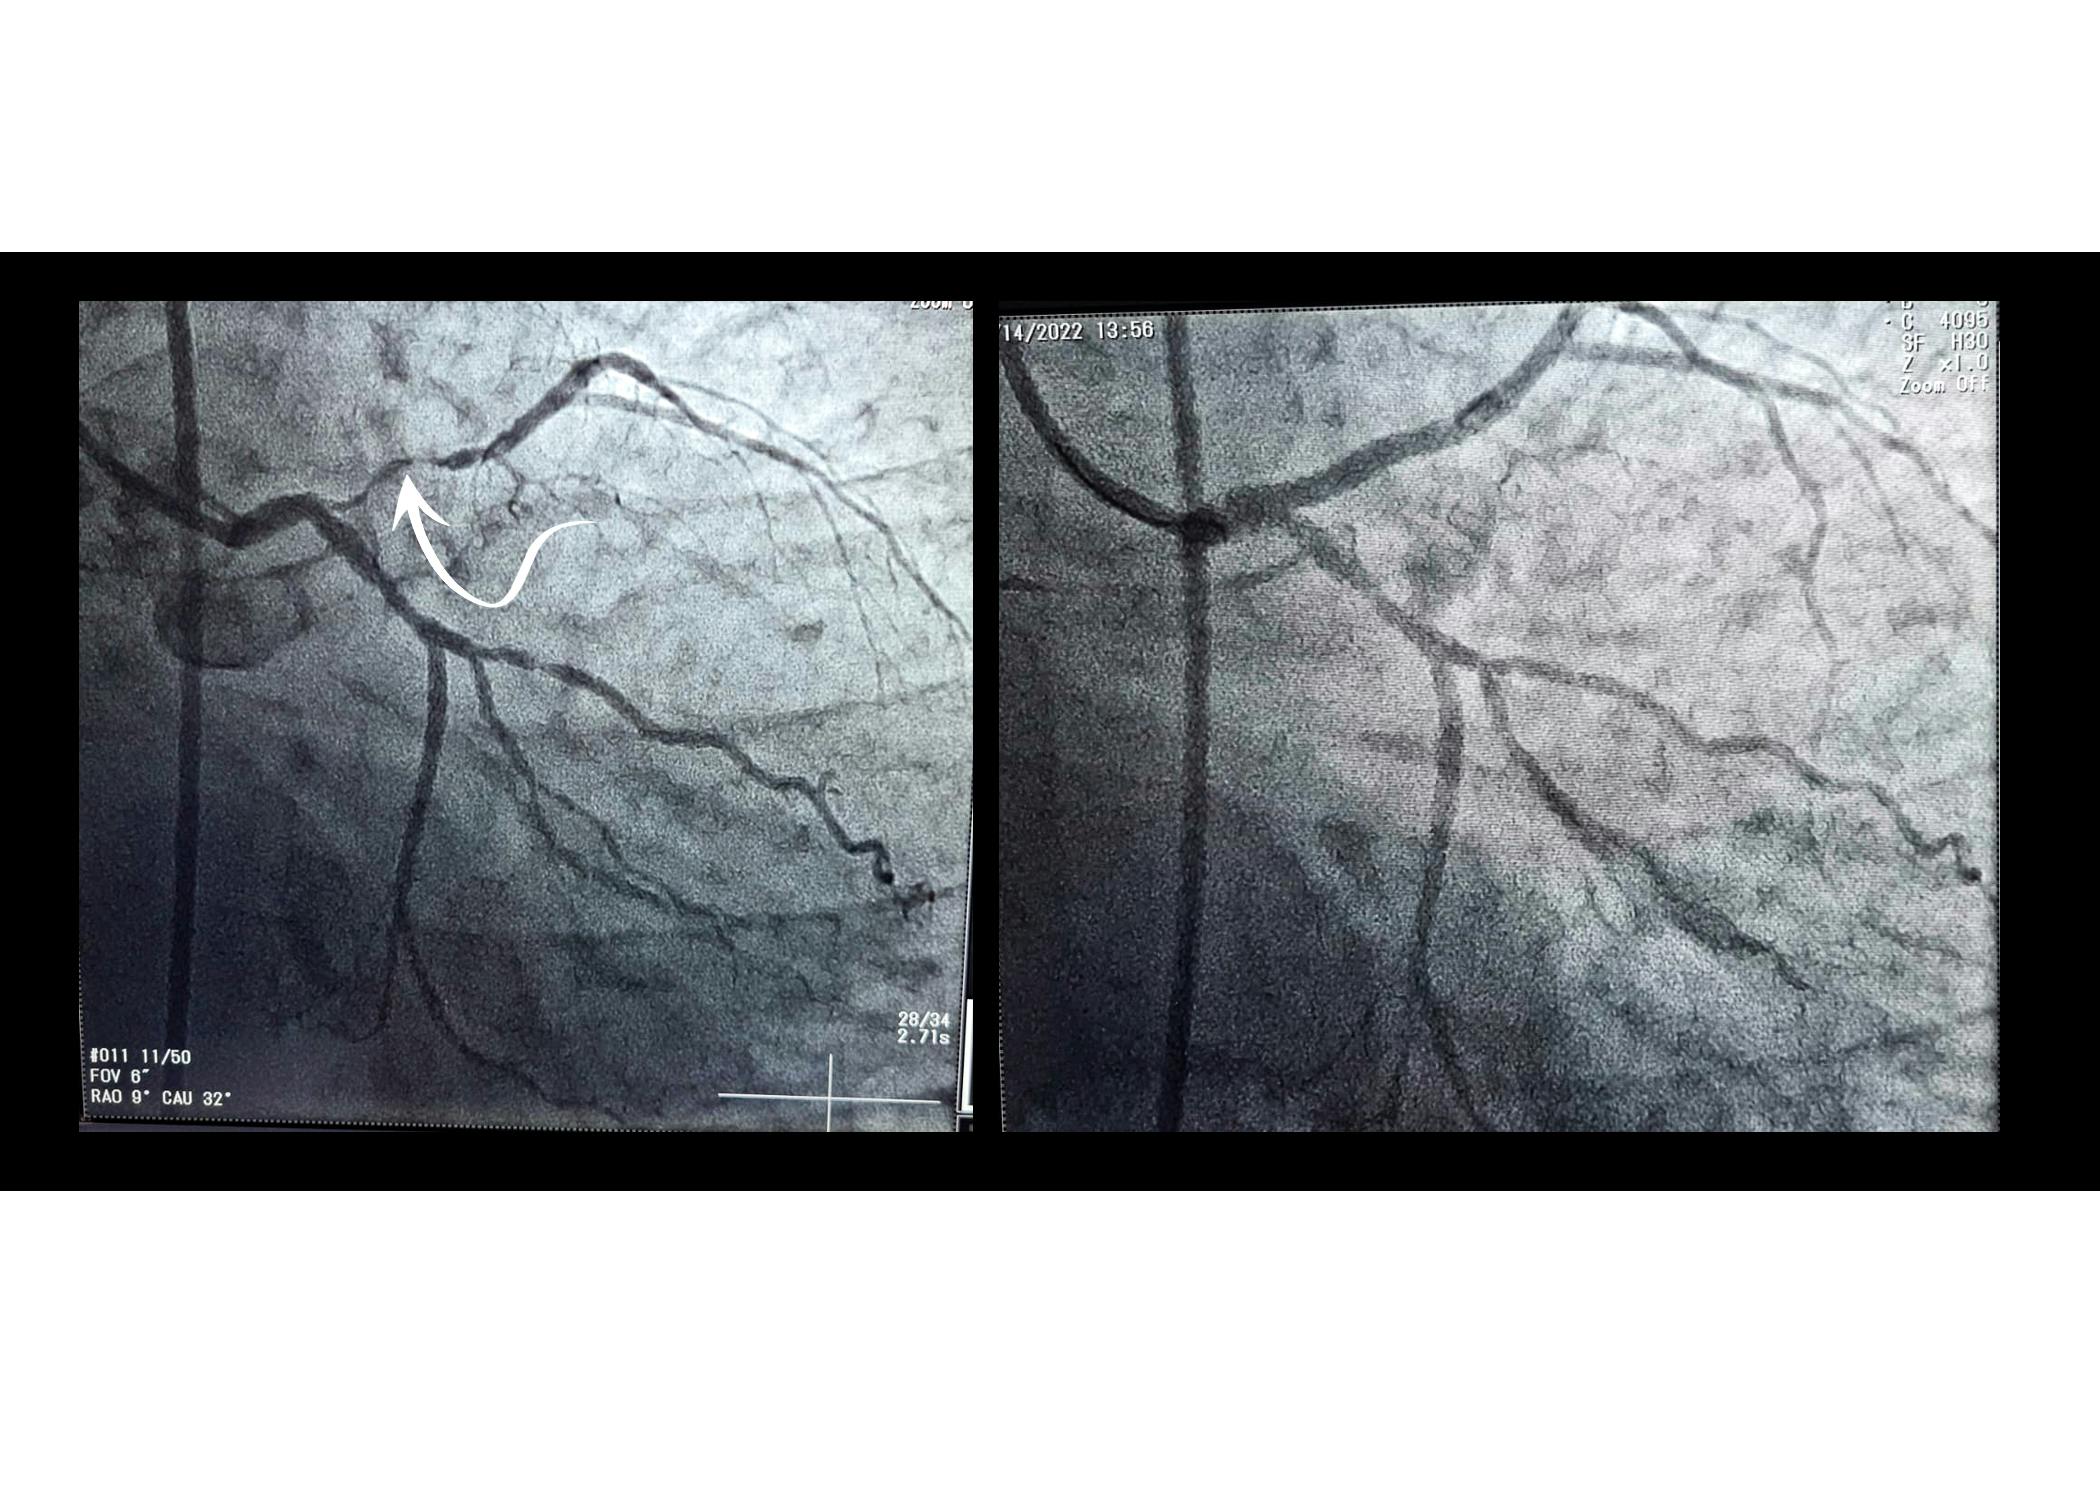

După ce a efectuat puncția la nivelul arterei femurale și a navigat prin interiorul vaselor de sânge până la nivelul arterelor inimii, doctorul Leornard Licheardopol a injectat substanța de contrast și a observat că la nivelul arterei descendente anterioare există o stenoză importantă care îngustează vasul și îngreunează circulația sângelui.

După diagnosticul concret, doctorul Leornard Licheardopol, medic intervenționist la ARES Tulcea a implantat un stent metalic la nivelul stenozei și astfel a redat circulația normală a sângelui la acest nivel.

Această intervenția poartă numele de angioplastie coronariană, iar stentul este un dispozitiv metalic de dimensiuni foarte mici care ajunge să fie implantat în interiorul unui vas de sânge unde există o stenoză. Stentul aplatizează depunerile cumulate pe pereții arterei și permite sângelui să aibă un flux normal. Prin montarea acestuia în artera coronară, stentul menține vasul de sânge permeabil, iar pacientul este salvat de la infarctul miocardic acut.